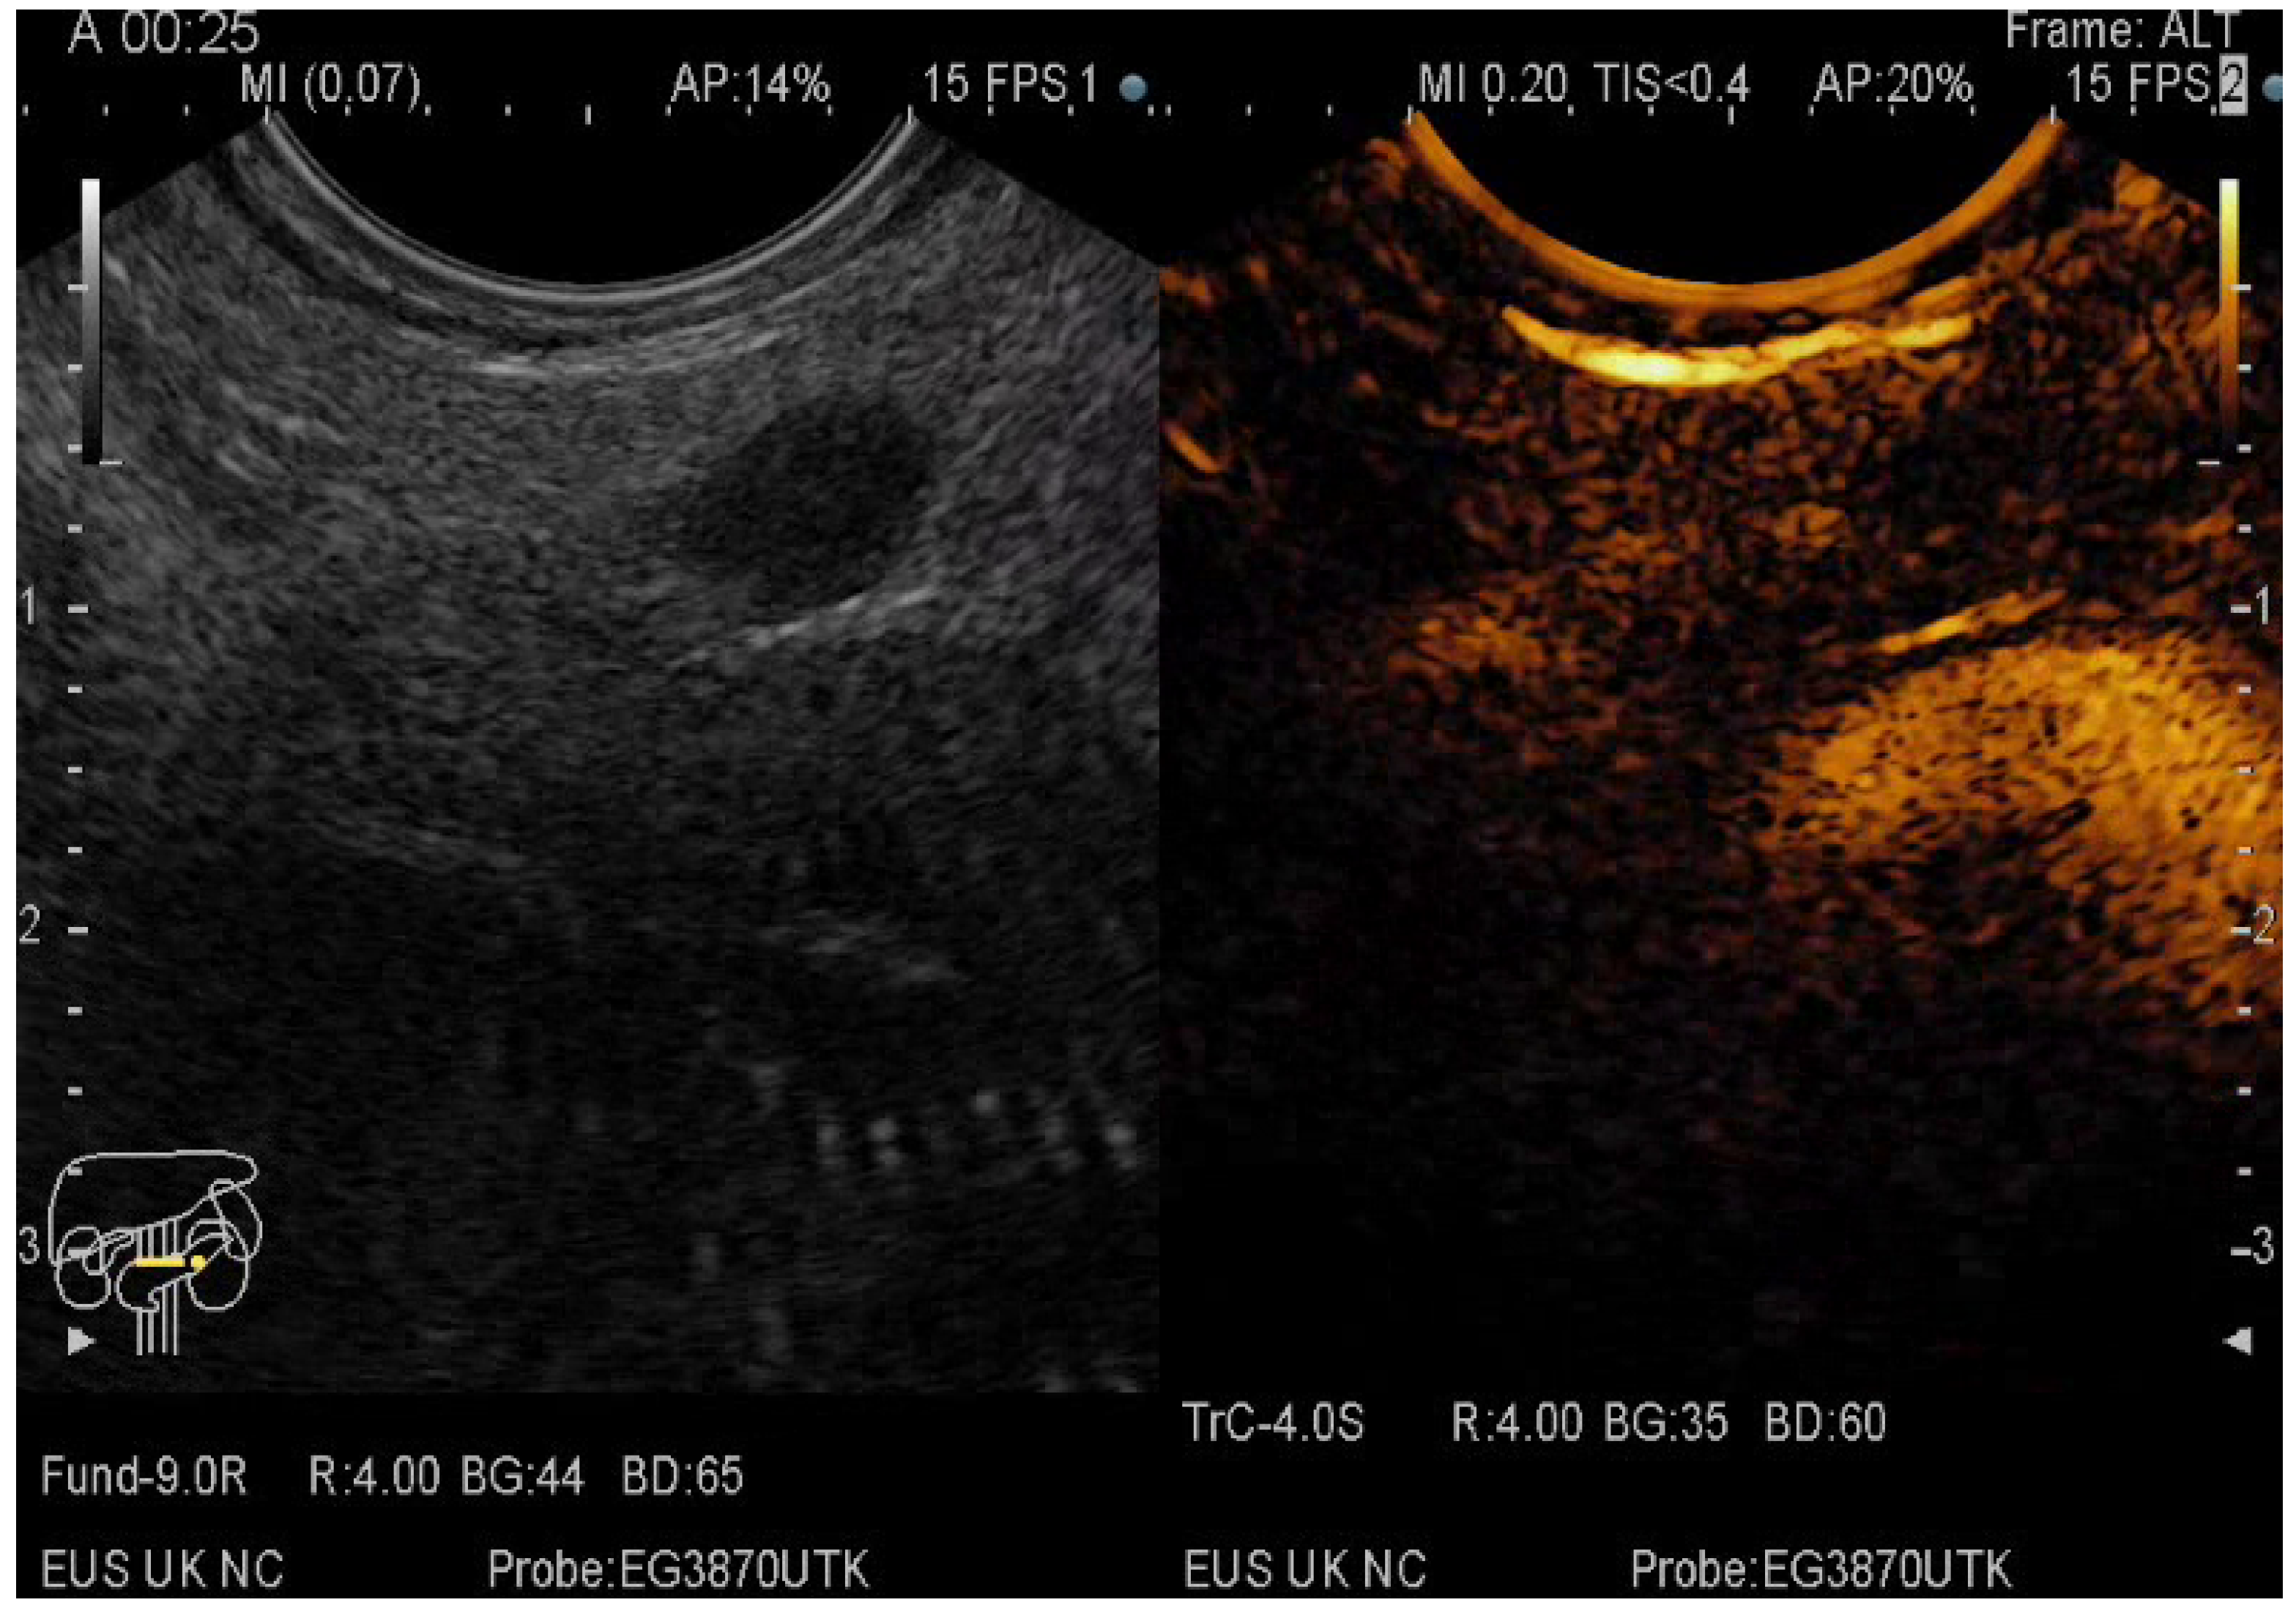

The pancreatic masses where located as it follows: 2/3 at the head level and 1/3 at the level of the body and tail. The size of the pancreatic masses ranged from 10 to 78 mm, with an average diameter of 35 mm. For obtaining the core tissue, fanning technique was applied with a mean number of needle passes of 2 and a range from 2 to 5 passes. Final pathology revealed pancreatic ductal adenocarcinoma–PDAC (149) (Figure 3), mass-forming pancreatitis–MFP (57) (Figure 4), pancreatic neuroendocrine tumors–pNETs (23) (Figure 5 and Figure 6), undifferentiated carcinoma (17), mucinous carcinoma (5), and pancreatic metastasis (5).

Figure 5.

CE-EUS image of a pNET revealing an isoenhancing solid mass in the arterial phase and a discrete wash-out in the venous phase.

In 48% of the cases, the pancreatic lesion was described as hypoenhancing, with a final diagnosis of malignancy. Regarding the enhancement patterns, hypovascularity in both arterial and venous phase was associated with PDAC, hypervascularity or isovascularity in both phases were associated with either MFP or NETs, whereas the carcinomas were hypervascular (Table 6). A heterogeneous appearance with non-enhancing areas was noted in a small percentage of the hypoenhancing lesions and it might suggest necrosis. The overall diagnostic accuracy was 91%.